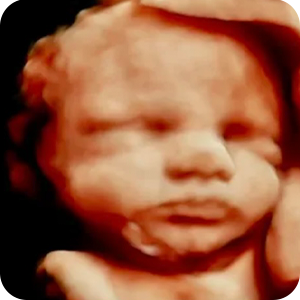

Elective 2D, 3D and 4D Ultrasounds in Tampa.

See your baby in 2D, 3D, and 4D. Experience the joy of meeting your baby before birth. Our elective ultrasounds are designed to create unforgettable moments for families. Enjoy our cozy environment of peace in an ultrasound in Tampa or Central Florida.

Our elective 4D sessions capture your baby’s real movements and transform them into breathtaking 8K baby portraits, memories you can keep forever.